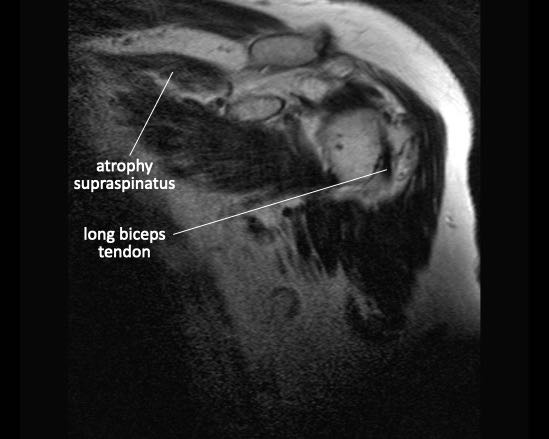

Teo cơ – Dấu hiệu tiếp tuyến (Tangent sign)

Phương pháp đánh giá teo cơ của Warner dựa trên hình ảnh mặt phẳng chéo đứng dọc (oblique sagittal) ở vị trí trong so với mỏm quạ.

Một đường thẳng được vẽ từ bờ mỏm quạ đến đỉnh dưới của xương bả vai, và từ gai xương bả vai đến mỏm quạ.

Nếu cơ lồi lên trên đường này, không có teo cơ.

Nếu cơ nằm ngay dưới đường này, có teo cơ mức độ vừa.

Nếu hầu như không thấy cơ, có teo cơ mức độ nặng.

Hình bên trái cho thấy giải phẫu cơ bình thường trên ảnh mặt phẳng đứng dọc.

Hình bên phải là của bệnh nhân có rách toàn bộ chiều dày cả gân cơ trên gai và gân cơ dưới gai kèm co rút.

Có hình ảnh teo mỡ của cơ trên gai và cơ dưới gai.

Trên các chuỗi xung có ức chế mỡ, việc đánh giá teo cơ và thay thế mỡ có thể gặp khó khăn.

Hình ảnh

Trên hình ảnh có ức chế mỡ bên trái, có thể nhận định nhầm rằng cơ trên gai bình thường (mũi tên xanh lam).

Tuy nhiên, trên hình ảnh không có ức chế mỡ, có thể thấy rõ tình trạng teo cơ nặng và thay thế mỡ với tín hiệu cao (mũi tên xanh lam).

Mũi tên đỏ chỉ vị trí rách toàn bộ chiều dày của gân cơ trên gai.